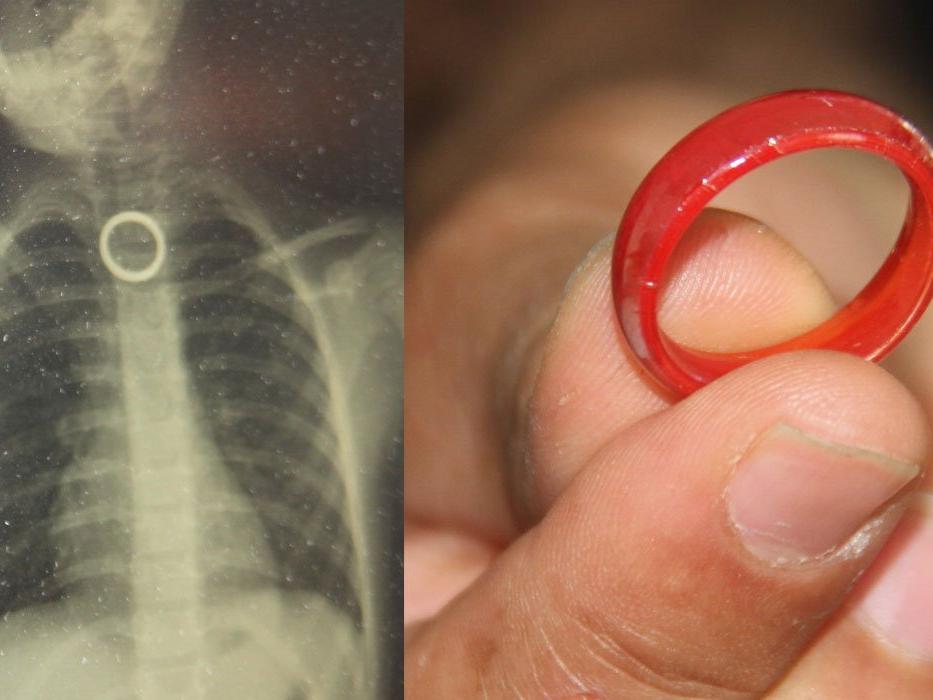

Elazığ’da evde oyun oynayan 3 yaşındaki çocuk, yakınında bulunan yüzüğü yuttu. Durumu fark eden ebeveynler çocuğu hemen Fırat Üniversitesi Hastanesine getirerek Çocuk Gastroenteroloji Ana Bilim Dalı Başkanı Prof. Dr. Yaşar Doğan’a gösterdi.

Burada yapılan tetkiklerde yutulan yüzüğün yemek borusu birinci darlık kısmında takılı kaldığı görüldü. Hemen Çocuk Endoskopi Ünitesine alınan 3 yaşındaki çocuğun boğazındaki yüzük yapılan endoskopik yöntemle çıkartıldı.

"Bu hastamız akşam saatlerinde boğazına yabancı cisim yutma yakınmasıyla ailesi tarafından hastanemize getirildi. Yaptığımız incelemeler neticesinde özellikle yemek borusunun birinci darlık kısmında yüzüğü benzer bir yabancı cisim gördük.

İlk geldiğinde hasta yeni beslendiğinden dolayı endoskopi için açlık süresi bekletildi. Ondan sonra gerekli olan endoskopi işlem yapılarak oradaki yabancı cisim çıkartıldı. Çıkarma işlemi başarılı bir şekilde yapıldıktan sonra aile 2 saatlik gözlemden sonra evine gönderildi.

Yerde buluğu yüzüğü yutan 3 yaşındaki çocuk ölümden döndü

Elazığ’da 3 yaşındaki çocuğun yerde bularak yuttuğu yüzük yemek borusuna sıkıştı. Yüzük, cerrahi operasyonla çıkartıldı.